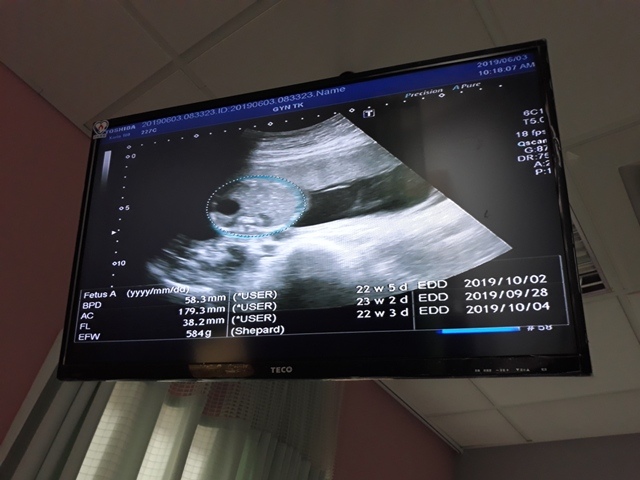

早上十點左右,和小純至澄清醫院做產檢,今日要做的是『妊娠糖尿病』的檢查(一般來說,妊娠糖尿病是24週 - 28週檢查,不過小純今天是第23週又3天,還沒到24週),首先我們先到抽血室去,護理師拿了五瓶裝的美達妍注射液讓小純喝,喝完之後一個小時以後再進行抽血。來之前小純有跟我說過,驗妊娠糖尿病要喝很甜的 糖水,但她今天喝了,感覺還好,不會很甜。

近五次產檢資料統計

| 日期/項目 | BPD | AC | FL | EFW | 心跳 |

| 2019年03月04日 | 無資料 | 無資料 | 無資料 | 無資料 | 無資料 |

| 2019年04月01日 | 28.9mm | 77.9mm | 14.2mm | 107g | 153 |

| 2019年04月29日 | 41.7mm(44%) | 125.7mm(61%) | 28.9mm(103%) | 241g(125%) | 150 |

| 2019年05月22日 | 53.4mm(28%) | 160.6mm(28%) | 34.6mm(20%) | 408g(69%) | 150 |

| 2019年06月03日 | 58.3mm(9%) | 179.6mm(12%) | 38.2mm(10%) | 584g(43%) | 157 |

| BPD:胎兒頭骨橫徑 AC:胎兒腹圍的長度 FL:胎兒大腿骨的長度 EFW:胎兒的體重 括弧內百分比為較上次產檢的成長比例 | |||||

今天關醫師也把4月22日所做的羊膜穿刺及羊水晶片的報告拿給我們,一切都正常。